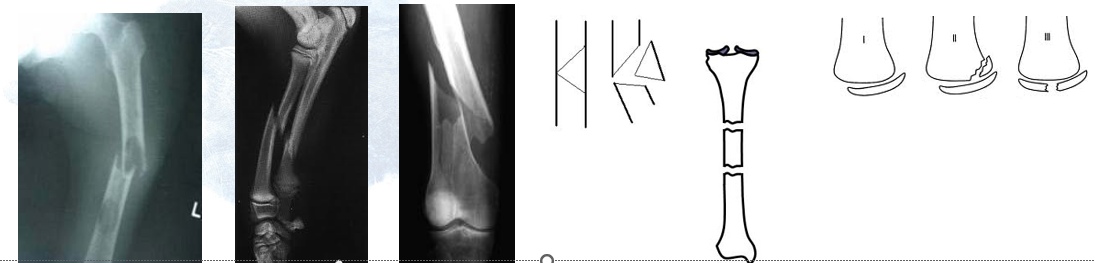

• Fracture Types

Complete

–Transverse – crosses diaphysis at  right angles to long axis

–Oblique – crosses diaphysis at 45  degree angle

–Spiral – due to excessive torsion –  fracture spirals up long axis

–Comminuted – break resulting in  production of more than two pieces

•Butterfly – wedge of bone separates  from fractured ends

•Segmental -  three segments

–Epiphyseal – occurs at ends of long  bones, can separate epiphysis from  diaphyseal metaphysis

• Directionality of Fracture

•Blunt force injuries can be examined in terms of  tension/compression for directionality of fracture

•Bone is stronger in compression than tension

•Bone usually fails under tension (some unique  circumstances)

•These simple principles often allow for fracture  directionality to be determined.

–Butterfly fracture example

•Compression at site of impact, tension occurs at opposite  side. Bone fails under tension. Fragment sheers towards  impact site